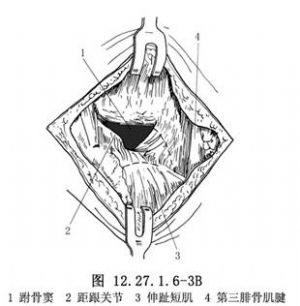

5.2.7.3 3.显露跟骰及距舟关节

将伸趾短肌在跟骨前外附丽处切开,向远侧翻开,注意尽量保持其完整和血液循环,以便缝合时覆盖死腔及骨面。切开跟骰关节囊以显露跟骰关节,剥离距骨颈上外部的骨膜,切开距舟关节囊以显露距舟关节(图12.27.1.6-4)。